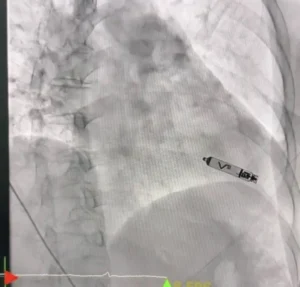

ผู้ป่วยเป็นหญิงอายุ 56 ปี ได้รับการวินิจฉัยว่าเป็นโรคหัวใจเต้นช้าผิดจังหวะชนิดสมบูรณ์ (Complete Heart Block) ซึ่งจำเป็นต้องใส่เครื่องกระตุ้นหัวใจเพื่อช่วยควบคุมจังหวะการเต้นของหัวใจ โดยคณะแพทย์ได้เลือกใช้เครื่องกระตุ้นหัวใจชนิดไร้สาย (Leadless Pacemaker) ซึ่งเป็นเทคโนโลยีใหม่ล่าสุด ทำการใส่ผ่านสายสวนหลอดเลือดเข้าสู่หัวใจโดยตรง

เทคโนโลยีดังกล่าวมีข้อดีคือ ไม่มีสายไฟเชื่อมต่อกับตัวเครื่อง ลดความเสี่ยงต่อการติดเชื้อ ลดภาวะแทรกซ้อนจากสายเครื่องกระตุ้นหัวใจ และช่วยให้ผู้ป่วยฟื้นตัวได้เร็วขึ้น